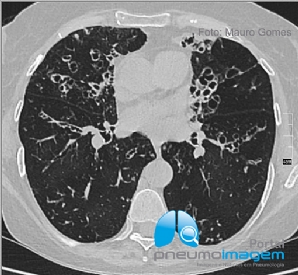

CASO CLÍNICO #52

Paciente do sexo feminino, 46 anos, submetida a transplante de medula óssea há 2 meses, apresenta-se com dispneia, tosse seca e dessaturação. Qual o provável diagnóstico? Deixe seus comentários abaixo! ***** A 46-year-old female patient who underwent bone ma...